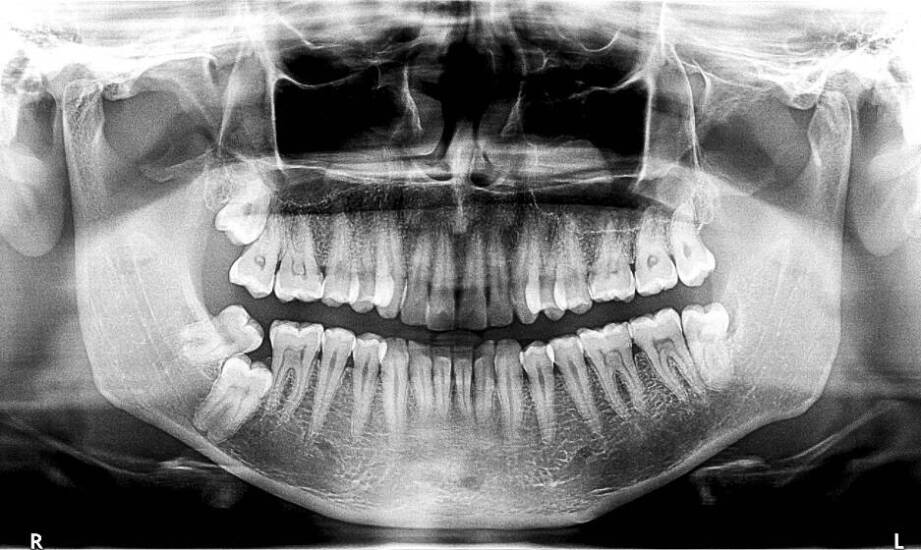

Diagnostyka CBCT, czyli tomografia komputerowa o dużej rozdzielczości, odgrywa kluczową rolę w planowaniu leczenia stomatologicznego. Dzięki trójwymiarowym obrazom specjaliści mogą dokładniej ocenić stan uzębienia oraz struktury anatomiczne pacjenta. To innowacyjne podejście rewolucjonizuje proces diagnozowania i leczenia, wpływając na precyzję diagnozowania i skuteczność terapii. W artykule omówimy różne aspekty tej technologii, jej zalety w porównaniu do tradycyjnych metod obrazowania, zastosowanie w różnych dziedzinach stomatologii oraz korzyści dla pacjentów i dentystów. Zachęcamy do lektury!

Tomografia komputerowa o stożkowej geometrii ma istotne znaczenie dla zapewnienia pomyślnego przebiegu terapii stomatologicznej przy planowaniu wszczepów. Dzięki tej technologii lekarze mogą dokładnie ocenić warunki anatomiczne pacjenta, co pozwala na minimalizację ryzyka powikłań oraz zwiększenie szans na powodzenie zabiegu. Wszczepienie implantów wymaga precyzyjnego planowania, a szczegółowe obrazy uzyskane za pomocą CBCT umożliwiają identyfikację struktur kostnych i miękkotkankowych. To pozwala na optymalne umiejscowienie implantów oraz dobór odpowiednich rozmiarów i kształtów. W rezultacie pacjenci mogą cieszyć się trwałymi i estetycznymi rozwiązaniami protetycznymi. Warto podkreślić, że dentysta w Brzesku wykorzystujący CBCT w swojej praktyce zapewnia najwyższy standard opieki stomatologicznej. Technologia ta nie tylko poprawia jakość leczenia, ale również przyczynia się do zmniejszenia dyskomfortu odczuwanego przez osoby korzystające z zabiegów dentystycznych. Dzięki nowoczesnym metodom znieczulenia i sedacji oraz przyjaznej atmosferze w gabinetach, klienci mogą czuć się bezpiecznie i komfortowo.

Tomografia CBCT odgrywa kluczową rolę w chirurgii stomatologicznej, umożliwiając precyzyjne planowanie zabiegów oraz ocenę trudnych przypadków. Dzięki trójwymiarowym obrazom chirurdzy mogą lepiej zrozumieć skomplikowane struktury anatomiczne, co przekłada się na bezpieczeństwo i efektywność operacji. Technologia ta zmienia oblicze chirurgii, pozwalając na dokładniejsze analizy i unikanie potencjalnych powikłań. Specjaliści w Brzesku wykorzystują ją do planowania implantów, usuwania zębów mądrości czy leczenia zmian patologicznych. Takie podejście sprzyja indywidualnemu traktowaniu pacjentów oraz optymalizacji przebiegu zabiegów. Warto podkreślić, że tomografia CBCT jest mniej inwazyjna niż tradycyjne metody obrazowania, co redukuje dyskomfort osób korzystających z usług dentystycznych. Zastosowanie tej technologii w chirurgii stomatologicznej świadczy o zaawansowaniu lokalnych gabinetów oraz ich dbałości o dobrostan klientów. Wybierając dentystę w Brzesku, warto zwrócić uwagę na ofertę usług opartych na nowoczesnych rozwiązaniach technologicznych, takich jak diagnostyka radiologiczna czy leczenie laserowe.

Diagnostyka CBCT w endodoncji i ortodoncji ma istotne znaczenie w dokładnym identyfikowaniu problemów związanych z kanałami korzeniowymi oraz opracowywaniu planów leczenia ortodontycznego. Dzięki zaawansowanej technologii lekarze uzyskują precyzyjne obrazy struktur zębowych, co pozwala na lepsze zrozumienie stanu zdrowia pacjentów. W przypadku endodoncji umożliwia to identyfikację anomalii anatomicznych oraz ocenę stopnia zaawansowania zmian chorobowych. Natomiast w ortodoncji wspiera projektowanie aparatów ortodontycznych i monitorowanie postępów terapii. Korzyści płynące z zastosowania CBCT są niezaprzeczalne, a dentysta oferujący usługi w Brzesku zapewnia kompleksowe leczenie oparte na nowoczesnych technologiach. Warto skorzystać z oferty gabinetów stomatologicznych wykorzystujących diagnostykę CBCT dla uzyskania najlepszych efektów terapeutycznych.